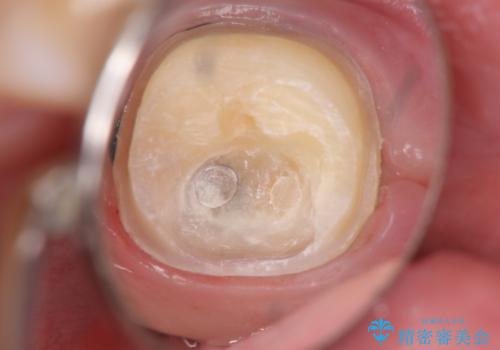

- 奥歯がしみるとのことで来院されました。

検査の結果、古い詰め物の裏側に虫歯ができていること(二次う蝕)が確認されたため、治療していくこととなりました。